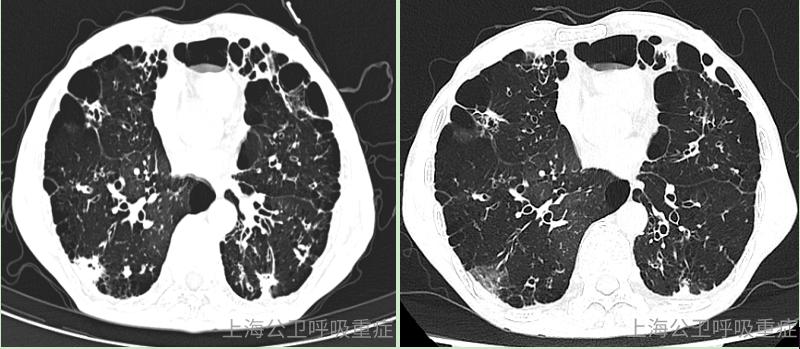

肺大泡怎么办?

ct片示徐大叔多发肺大泡形成

肺气肿肺大泡